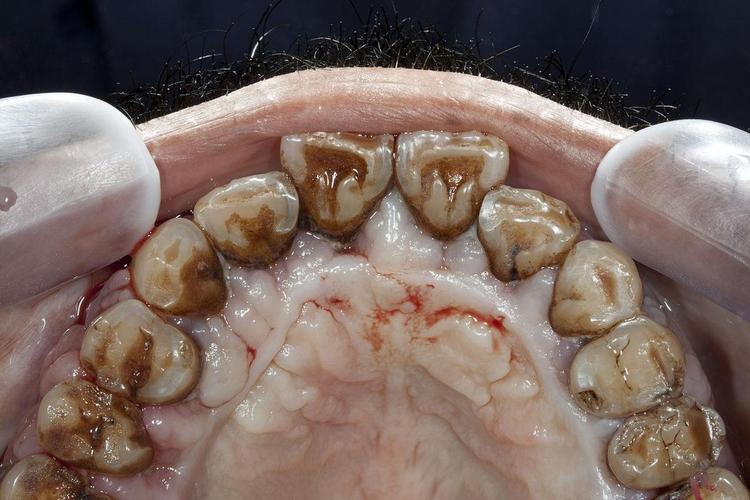

- 牙龈组织健康问题: 重度牙周炎常伴随牙龈退缩、牙周袋深、牙龈炎症明显,健康的牙龈组织对于封闭种植体颈部、防止细菌入侵至关重要,炎症的牙龈组织难以形成良好的生物学封闭。

- 牙龈没有明显红肿、出血。

- 牙周袋深度在可接受范围内(lt;5mm)。

- 没有活动性骨吸收。

- 患者能很好地维护口腔卫生。